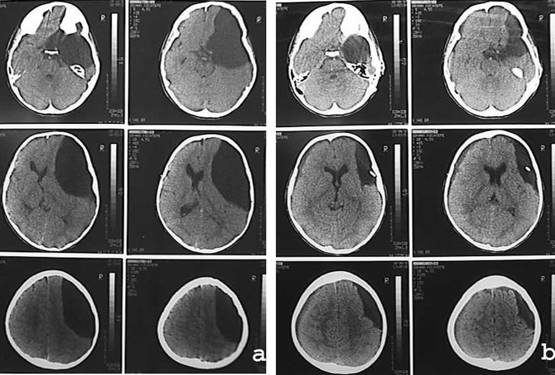

Genellikle kist içine takılan şant kist içindeki sıvıyı karın boşluğu içine boşlamasını ve oradan da tekrar kana karışmasını sağlar (Resim 4). Şant hemen hemen ömür boyu kalacaktır ve bu nedenle beyin karıncıklarına takılan şantlarda olduğu gibi tıkanma, enfeksiyon, kopma ve kırılma gibi aksilikler ortaya çıkabilir. Ameliyat olarak riski çok az olmasına karşın şantın uzun dönemde riskleri fazladır.

Resim 4: şant sonrası araknoid kistin kaybolduğunu gösteren BT.

Kafatasının açılıp, ameliyat mikroskobu ile beyin tabanındaki normal BOS yolları ile kist arasında pencereler açılması bir diğer yöntemdir. Böylece kist içindeki basınçlı sıvı açılan pencerelerden normal BOS yollarına karışarak sonunda emileceği yere ulaşır. Kistler şant sonrasında olduğu gibi hemen küçülmezler. Daha uzun sürede bir derece küçülür fakat içinde basınçlı sıvı bulunmaz. Aynı işlem endoskop kullanılarak kafatasında sadece bir delikten yapılabilir. Endoskopik ameliyatta ise cilt kesisi 2-3 cm.dir. endoskopik girişim için özel eğitim ve deneyim gereklidir.

Resim 4: (a) Şant ameliyatı öncesi tip III şakak bölgesi araknoid kistin BTsi,

(b) şant ameliyatı sonrası kistin küçüldüğü görülmektedir.

Bu bölgedeki kistlerde açık cerrahi uygulanan hastaların yaklaşık 1/4’ünde yine şanta gereksinim duyulmaktadır.